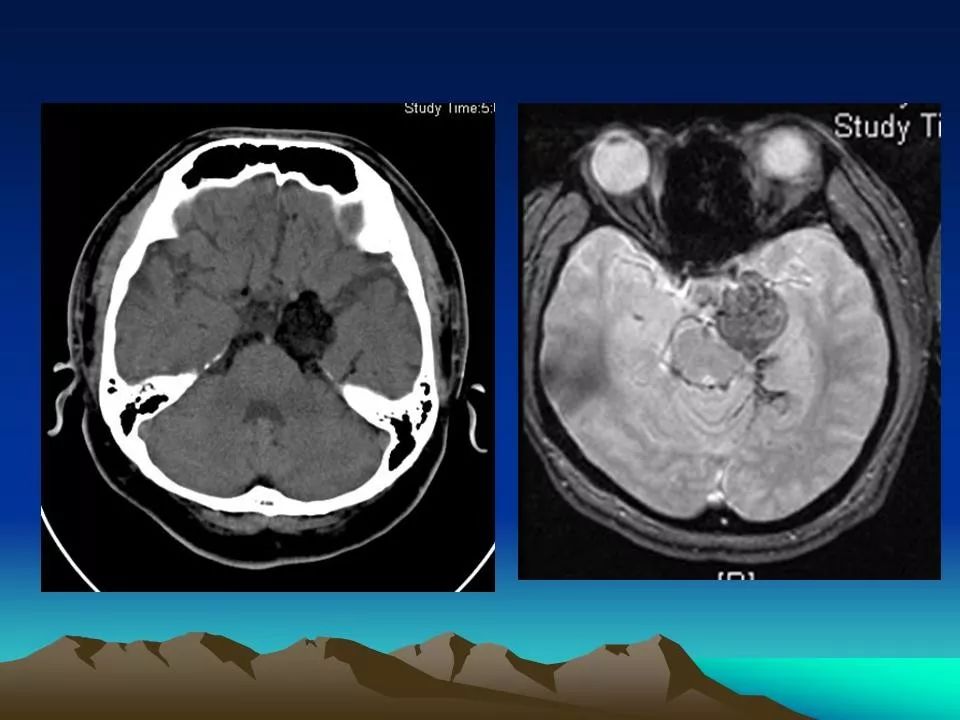

一例cpa巨大表皮样囊肿切除体会

一例被误诊的桥小脑角表皮样囊肿病例成功手术